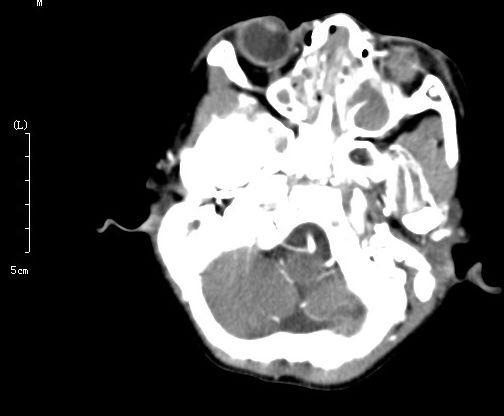

以下是引用winter在2006-8-27 18:54:00的发言:[br]男,7岁,外伤后左眼搏动、疼痛。增强扫描左侧海绵窦增宽,考虑颈动脉海绵窦瘘,双侧上颌窦蝶窦筛窦内的考虑为积血才是。